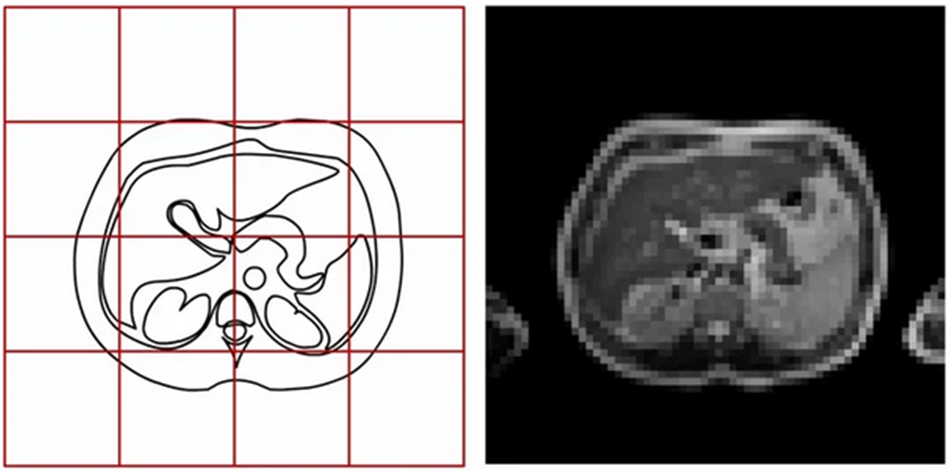

Область в пространстве глобальной СК, которую занимает отдельный слайс, определяется следующими параметрами изображения:

Начало координат (Origin) – координаты центра левого верхнего вокселя слайса в глобальной СК. DICOM-тэг (0020,0032) Image Position (Patient).

Интервалы (Spacing) – вектор расстояний между центрами пикселей вдоль каждого из измерений в единицах глобальной СК. DICOM-тэг (0028,0030) Pixel Spacing.

Размер (Size) – количество пикселей в каждом измерении. DICOM-тэги (0028,0010) Rows и (0028,0011) Columns

Матрица направляющих косинусов (Direction cosine matrix) — косинусы углов между осями локальной и глобальной СК. DICOM-тэг (0020,0037) Image Orientation (Patient). Хранится как одномерный вектор.

Начало координат локальной СК соответствует центру пикселя с координатами (0, 0). В отличие от представленного выше рисунка, такой пиксель обычно расположен в левом верхнем углу изображения. И соответствующие оси направлены вдоль первой строки (слева направо) и первого столбца (сверху вниз). Также на этом упрощенном рисунке не представлены z-координаты и направляющие косинусы с осью Z.

Объемность пикселявокселя приводит к тому, что реальная область пространства, которую занимает изображение, выходит за координаты крайних точек на полуинтервал по каждой оси. Это важно при расчетах и преобразованиях, где требуется высокая точность или точное сопоставление разных изображений в едином пространстве глобальной СК.